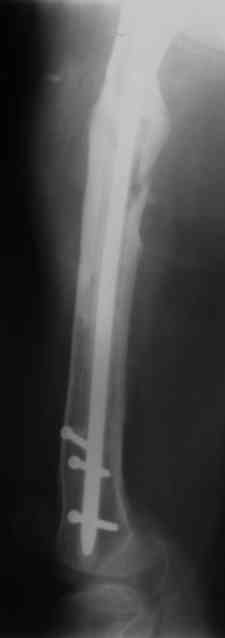

В настоящее время наш пациент ( см. http://weborto.net/forum/1177351385/) ходит с одним костылем. У него периодически открывается свищ на задне-наружной поверхности бедра с умеренным серозно-гнойным отделяемым. Температура тела и анализы нормальные. На рентгенограммах имеются признаки консолидации ложного сустава.

1, 2, 3, 4 - рентгенограммы бедра от 8 августа этого года (через четыре месяца после операции);